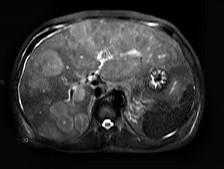

问题 男,58岁,上腹部胀痛不适2月余。MRI见肝内多发病灶。最可能的诊断是()

选项 A.结节型肝癌 B.肝转移瘤 C.肝癌并肝内转移 D.肝硬化并再生结节 E.未见异常

答案 B